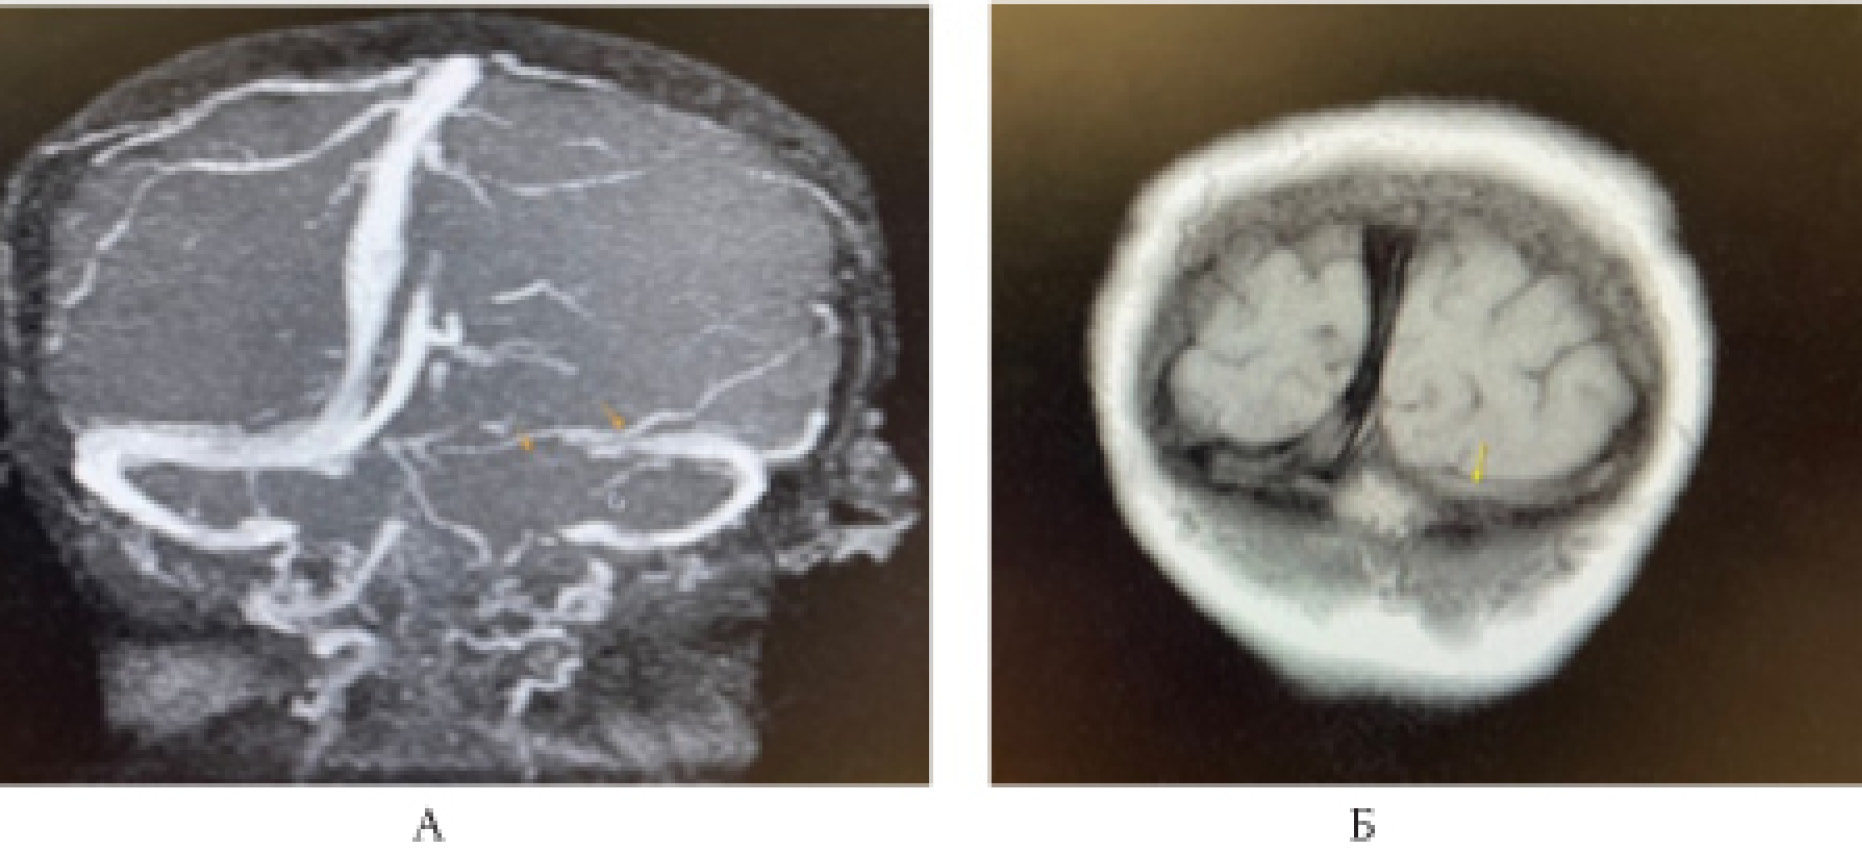

С целью определения состояния церебральных вен и синусов пациентке была проведена МР-веносинусография.

МР-веносинусография головного мозга от 07.09.2021 (рис. 3, 4).

Рис. 3. Магнитно-резонансная венографическая картина: отсутствие сигнала от кровотока по значительной части левого поперечного синуса (А), что не позволяет исключить тромбирование, либо замедление кровотока (Б), с учётом Cor N1 взвешенного изображения

Рис. 4. Магнитно-резонансные венографические признаки, подозрительные на единичный тромб в правом поперечном синусе (А). Однако, с учётом сырых данных (Б) и нативного Т2-взвешенного изображения, эти изменения являются арахноидальными грануляциями, врастающими в синус (В)